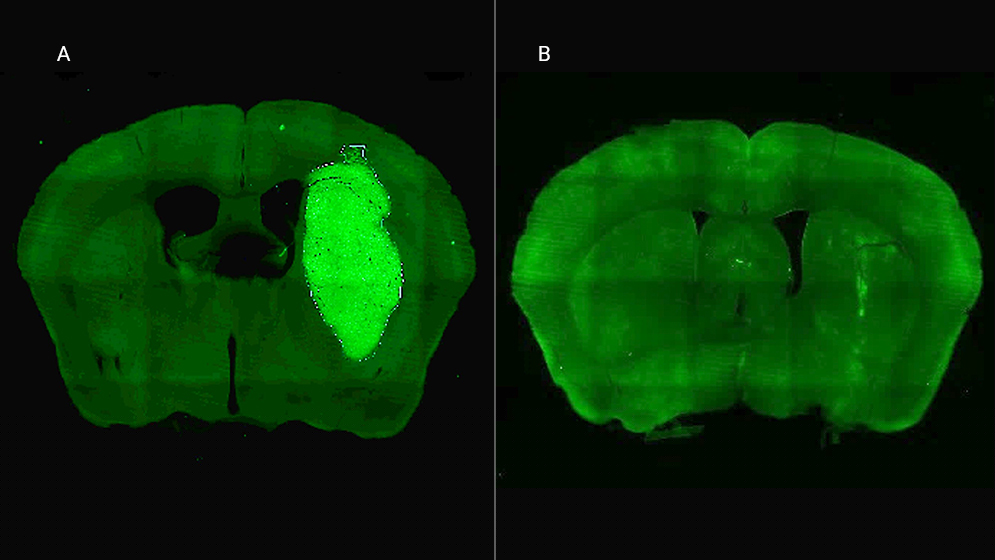

B) El tumor desaparece gracias a la administración de la estrategia terapéutica diseñada por los especialistas del CONICET.

El siguiente paso fue probar la estrategia en un modelo vivo. Para llevar el inhibidor P60 de forma sostenida y directa al tumor cerebral en ratones, el equipo desarrolló un ingenioso sistema de «delivery»: un virus modificado (un vector adenoviral) que, al ser inyectado en la zona, funciona como una bio-fábrica que produce el péptido P60 dentro de las células tumorales.

El resultado de la terapia combinada fue contundente y esperanzador. «Una inyección intratumoral del vector inhibió el crecimiento del tumor y mejoró notablemente la respuesta a la quimioterapia, llevando a la erradicación del tumor y sobrevida a largo plazo en un tercio de los ratones», revela Candolfi. Además, un dato clave es que no observaron efectos neurotóxicos, lo que sugiere un buen perfil de seguridad.